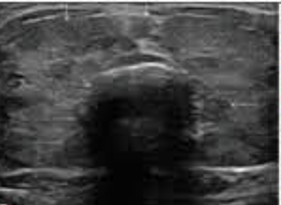

Siêu âm 2D

Kích thước tuyến giáp phì đại lan tỏa